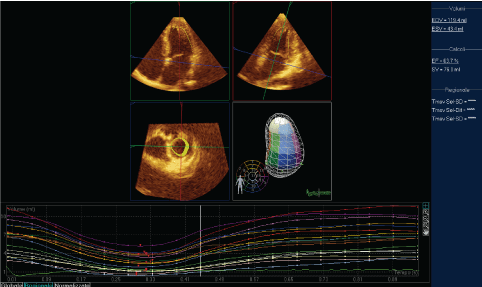

A 28-years-old woman was treated with i.m. injection of phloroglucinol for acute abdominal pain. A few minutes after administration of the drug, the patient had sudden chest discomfort and pain in the left arm, shortness of breath, sweating and palpitations, generalized erythema and cutaneous rashes that justified admission to Emergency Room. On physical examination, arterial blood pressure was 95/70 mmHg and pulse rate was 105 beats/min. Cardiovascular auscultation demonstrated no additional heart sounds. A clean reduction of arterial oxygen saturation was present. Blood tests revealed troponin I value of 2.5 ng/ml. White cell count was 15.51 × 109/l; C-reactive protein was 168 mg/dl. 12-leads ECG evidenced sinus rhythm and S-T depression (2 mm) in leads II, III, aVF (Figure 1). Treatment for anaphylaxis was started, with intravenous administration of hydrocortisone, diphenhydramine and bronchodilators, followed by improvement in cutaneous rashes, dyspnea, erythema and chest discomfort. 2D echocardiography did not reveal any valvular disease or contractility disorders, Simpson's %EF also was within normal limits. Normal ejection fraction, along with absence of wall motion abnormalities or contractile dysfunction was confirmed via 3D transthoracic echocardiography (Figure 2). Afterwards, the patient was transferred to the Coronary Intensive Care Unit due to a diagnosis of acute coronary syndrome and subsequently received 300 mg of ASA, 300 mg of clopidogrel and atorvastatin 40 mg PO. At the preangiographic treatment, 5000 IU heparin was given intravenously. Next, the patient underwent cardiac catheterization for coronary angiography. The procedure revealed no significant stenosis in the left anterior descending artery and its branches, circumflex artery or right coronary artery (Figure 3). On the basis of angiographic findings, a diagnosis of pure vasospasm was considered likely [4], and a diagnosis of KS was made on account of cutaneous and respiratory symptoms which resolved after bronchodilators, hydrocortisone and diphenhydramine. Prior to discharge, the repeat ECG revealed resolution of S-T segment depression, while troponin returned to normal values. Subsequently, the patient was discharged on day five of hospital admission.

Figure 2: Three-dimensional echocardiography of Left Ventricle (LV). EDV (End Diastolic Volume): 119.4 ml; ESV (End Systolic Volume): 43.4 ml; EF (Ejection Fraction): 63.7%; SV (Stroke Volume): 76.0 ml. The silhouette of LV in systole and diastole is also recorded. Uniform motility of LV fibers (below). View Figure 2